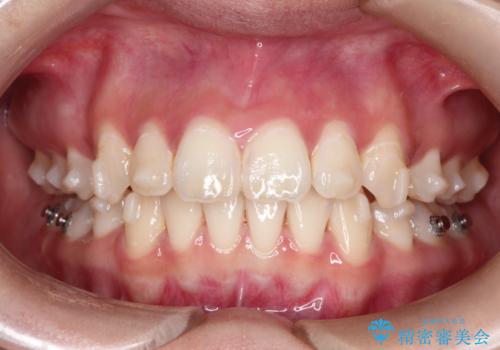

【インビザライン】シザーズバイト、抜歯矯正

- オープンバイトを主訴に来院された患者様です。

抜歯を行うことで、インビザラインを用いて前歯を下げることができ、同時にオープンバイトを改善することができました。

今回はインビザラインのみで治療を終了することができました。